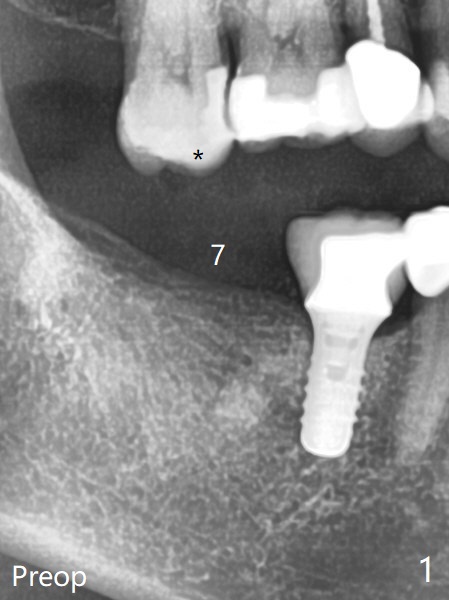

61岁女右下7导板钻洞,第一个钻头(环形钻)就有困难入位,部分磨去对合7近中腭侧牙尖(图一:*),钻头入位就好多了(图二:^,对比)。钻洞时发现骨质密度中等,所以最后钻头直径4.5毫米。不过无法用手植牙工具旋入植体,使用5.0毫米功螺纹钻头后,手工具就好用了,植体植入一定深度,扳手有空间插入,最后扭力30Ncm。第二个问题,当按照设计深度植入植体,用探针检查颊侧好像没有骨壁;加深大约0.5毫米(仿佛没有取到目的,颊侧骨板不明显)后,使用6毫米profile钻头,插入5.5x3毫米愈合基台(图二,三),在基台和颊侧牙龈之间植入异体骨粉,但愿帮助颊侧骨板再生。术后一周内敷料脱落,颊侧伤口愈合,好像骨粉没有流失。术后2.5月愈合基台脱落,换至小号基台(4向毫米),仍旧疼痛,休息2分钟,手拧紧,拍摄根尖片,仿佛就位(图四)。准备一周后调换稍微大,例如,4.8毫米基台。术后3.5个月,5.2毫米基台好像没有就位(图五:<),可能与远中牙槽嵴接触(*)。小一号基台仿佛就位(图六),与远中牙槽嵴无接触。术后4个月粘固后基台螺丝拧紧30Ncm。术后8个月,也就是粘固后4个月,牙槽嵴似乎试图覆盖植体平台(图七:箭头)。